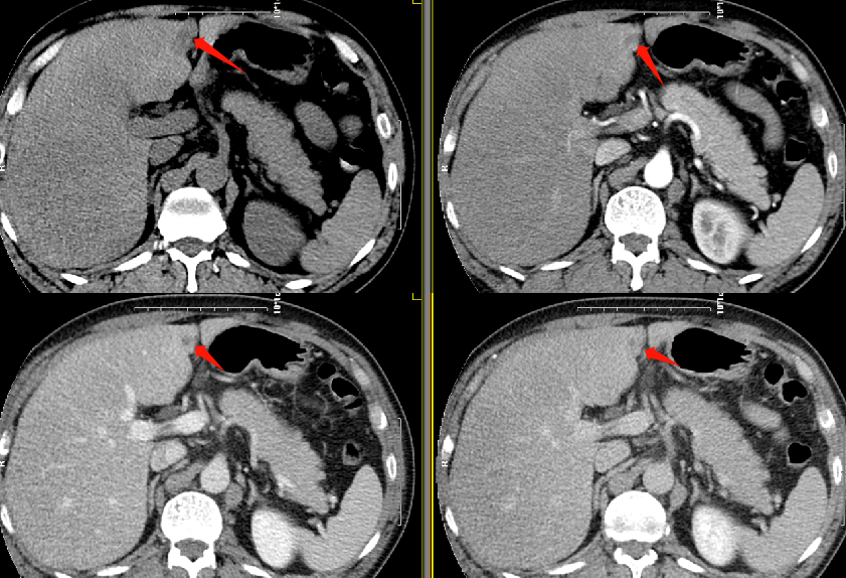

肝脏CT平扫:肝左内叶、左外叶镰状韧带旁可见斑片状低密度影,边界清,长径约1.5cm。

肝脏MR平扫及增强:肝左内叶及左外叶镰状韧带旁可见斑片状稍长T1、等T2信号,长径约1.6cm,病灶于T1WI反相位较同相位信号减低,增强各期均呈低信号表现。脾脏增大。

影像表现:病灶多较小,最大径通常小于2.5cm,可为不规则形、类圆形或三角形。根据平扫及增强扫描图像上的密度及其变化情况,将其分为A型和B型。

A型:占大多数,平扫呈等密度 ,动脉期呈等密度或略低密度,门脉期呈低或稍低密度且门脉期显示最清晰,平衡期及延迟扫描呈等或略低密度。(见下图所示)

B型:平扫、各期增强均呈低或略低密度。(见下图所示)